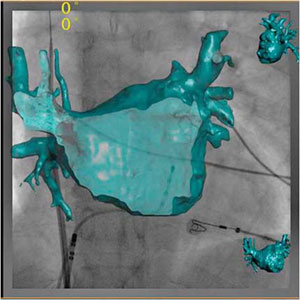

上記のCT TrueViewをさらに発展させたものが,現在開発中の“CTO Navigator”である。このアプリケーションでは,CAGや透視画像に冠動脈3D CT画像を重ね合わせることによって,さらに,直感的に治療戦略のイメージを具体化させることができる(図4)。

このような3D画像と透視画像とのフュージョンにより,直感的かつ正確に病変形態を把握し,治療を進めていくことができるため,PCIをより迅速かつ正確なものとさせる。

図4 CTO Navigator(W.I.P.)

フィリップスではこれらの要求に応えるため,新たに“EP Navigator”を開発した。EP Navigatorは,心臓CT検査で得られる左心房の3D CT画像を透視画像上に重ね合わせ,ロードマッピング操作を可能とした。このアプリケーションにより,すべてのカテーテルの位置と左心房の解剖学的な情報を合わせて,リアルタイムに画面上で確認できる。Cアームの角度変更,テーブルのパニング,SID,FOVの変化にも,リアルタイムで追従する(図5)。

また最新では,心臓CTデータによるマッピングに替わり,血管撮影装置の回転撮影より得られた3次元画像(3D-ATG)を使用したマッピングも可能となっている。図6のように,心臓CTと遜色のない画質で左心房の描出が行える。3D-ATGは,心臓CTによるEP Navigatorのように位置合わせの必要がなく,自動的に透視画像にオーバーレイされるため,正確で迅速な治療の支援となる。  今後,わが国でも増加が予想されるアブレーション治療に対して,EP Navigatorはさまざまな形で貢献できると考えられる。特に,手技時間の短縮によりスループットが向上し,潜在的な患者さまを含めた多くの症例を治療の対象にできることはメリットであろう。

図5 EP Navigator

3D画像をカットし,後壁の様子を確認しながらのカテーテル操作も可能である。